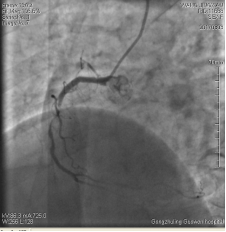

中日聯(lián)誼閆明洲教授向家屬交代病情及介入相關(guān)并發(fā)癥后,患者及家屬同意冠脈支架治療,過程順利,于右冠脈中段植入Firebird2 2.5*33mm 藥物洗脫支架1枚。

術(shù)前 術(shù)后

患者冠脈支架植入術(shù)后,胸骨后疼痛癥狀明顯好轉(zhuǎn),復(fù)查心電圖抬高的ST段回降。